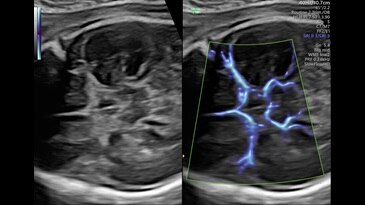

Circle of Willis shown with SlowflowHD in Dual Display